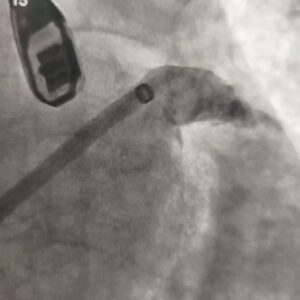

La intervención, que representa un avance significativo para la atención sanitaria local, fue realizada por el Dr. Darío Cavalié, cardiólogo intervencionista, y consistió en la oclusión de la orejuela de la aurícula izquierda.

El cardiólogo intervencionista detalló: “Más precisamente dentro de la aurícula hay un bolsillo que es donde se generan esos coágulos y nosotros mediante esta intervención fuimos a ocluir en una suerte de tapón, esa cavidad llamada orejuela”.